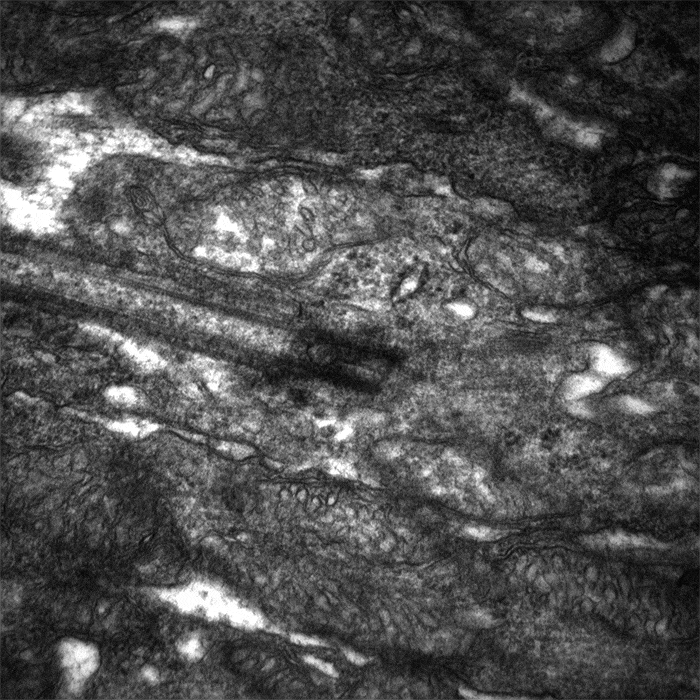

Photoreceptor Cilium Tilt Series